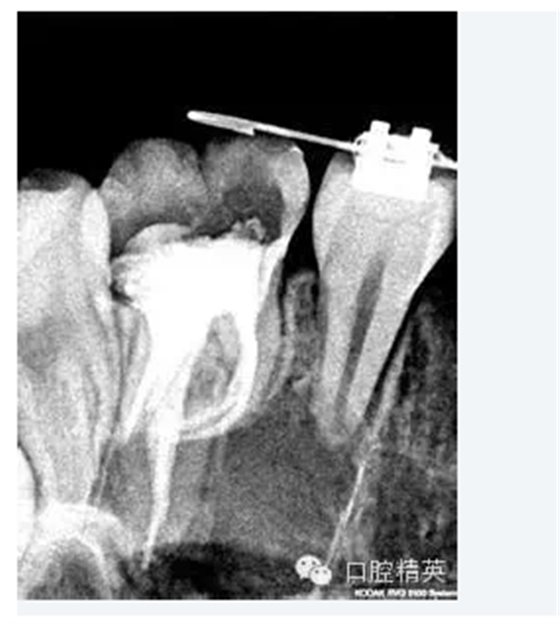

5.根管髓腔部分的預(yù)先擴(kuò)大可以幫助牙醫(yī)做出更明確的診斷。預(yù)先擴(kuò)大的根管髓腔部分可以容納較大型號(hào)的金屬根管擴(kuò)大器,X光片顯示更清晰;由于接觸頭更容易的與髓腔牙本質(zhì)接觸,電子根尖定位器的顯示也更明確。

2.確定根尖孔的合適開放根據(jù)X線片(RT)確定的根尖孔位置,將一柔軟的10號(hào)擴(kuò)孔銼輕輕推進(jìn)。為了保證根尖孔的良好開放,應(yīng)保證擴(kuò)孔銼尖端超過根尖孔1mm, 同時(shí)減少齲壞牙本質(zhì)碎霄的堆積 (在10號(hào)擴(kuò)孔銼其D1位置的直徑為0.12mm) ,輕輕的將之向前推進(jìn)1mm,以提供更大的空間,保證所有牙髓組織碎片、齲壞牙本質(zhì)碎霄的清除及沖洗液的自如進(jìn)出,同時(shí)降低根管堵塞的發(fā)生率。根尖孔完全開放或10號(hào)擴(kuò)孔銼向前推進(jìn)幅度不足1mm都是不可取的,因?yàn)榕R床研究表明:兩種選擇的治療結(jié)果都不甚理想。

3.工作長度經(jīng)驗(yàn)豐富的臨床牙醫(yī)可以根據(jù)以往經(jīng)驗(yàn)來判斷根管的工作長度。作為輔助手段,電子根尖定位器能提供更準(zhǔn)確、更可信、更有價(jià)值的工作長度信息,甚至在根管鈣化明顯或彎曲嚴(yán)重的病例也能對(duì)根尖孔進(jìn)行準(zhǔn)確定位。在操作過程中,切記一點(diǎn),電子根尖定位器只能作為X片的輔助手段,而不可完全代替?zhèn)鹘y(tǒng)X片的作用。當(dāng)根據(jù)X線片(RT)及電子根尖定位器,根管的工作長度都已得到準(zhǔn)確確定后,即可采取多種方法對(duì)根管的根尖側(cè)1/3進(jìn)行最后的擴(kuò)大完成。